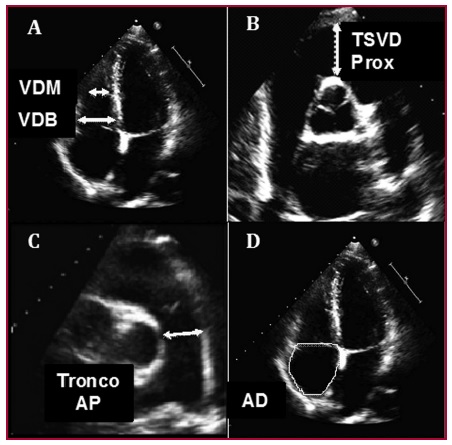

Materiales y métodos: Se incluyeron pacientes que asistieron al laboratorio de ecocardiografía y se excluyeron aquellos con miocardiopatías, deterioro de la función sistólica del ventrículo derecho o izquierdo, valvulopatías significativas, enfermedad pulmonar o presión sistólica pulmonar ≥ 45 mmHg. Se realizaron mediciones de ventrículo derecho basal, medio, tracto de salida proximal, área de auricula derecha y tronco de la arteria pulmonar, sobre la base de las recomendaciones de las guías.

Resultados: Estudio prospectivo, consecutivo, observacional y descriptivo de 1045 pacientes. Se observaron diferencias significativas en cada una de las variables de acuerdo con la distribución por cuartilos. Se demostró una correlacion positiva y estadísticamente significativa entre cada uno de los diámetros de las cavidades derechas y la superficie corporal. Se determinó el diámetro del ventrículo derecho indexado por superficie corporal. Para el ventrículo derecho basal se obtuvo un valor de 18,04 ± 5,1 (IC 95% 17,3-18,3); para el ventrículo derecho medial 13,40 ± 5,2 (IC 95% 13-13,7) y para el tracto de salida del ventrículo derecho 15,11 ± 5,54 (IC 95% 14,7-15,4).